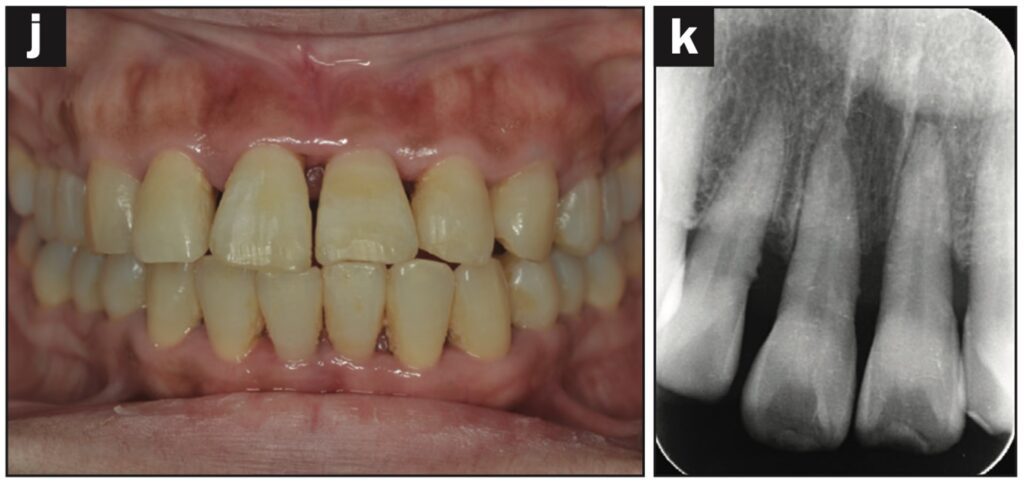

Bệnh nhân nữ 24 tuổi bị ngã khiến răng cửa giữa hàm trên bên trái bị lệch sang một bên. Sáng hôm sau, bệnh nhân đến phòng khám, được cố định bằng composite quang trùng hợp và lấy dấu.

Sáu tiếng sau, bệnh nhân quay lại và nhận hàm duy trì.

Bệnh nhân được hướng dẫn đeo hàm duy trì cả ngày trừ khi đánh răng. Các thử nghiệm độ sống tủy được thực hiện sau 1, 7, 14 và 21 ngày. Kiểm tra độ lung lay răng, gõ, sờ, thử tủy EPT và chụp X quang sau 28 ngày. Răng có độ lung lay +1 theo chiều ngoài trong và không có đáp ứng với thử nghiệm tủy EPT.

Ba tháng sau, răng đã được trám phục hồi và đáp ứng EPT (8/10). Tại thời điểm tái khám sau 4 tháng, răng đáp ứng với EPT (4/10). Sau 5 tháng, ghi nhận có lỗ dò. Răng không đáp ứng với EPT. Tổn thương quanh chóp được nhìn thấy trên X quang.

Răng được chẩn đoán là hoại tử tủy và điều trị tủy được thực hiện trong 2 lần hẹn. Một tháng sau (6 tháng sau khi chấn thương xảy ra), lỗ dò biến mất và chụp X quang cho thấy quá trình lành thương (hình 2).